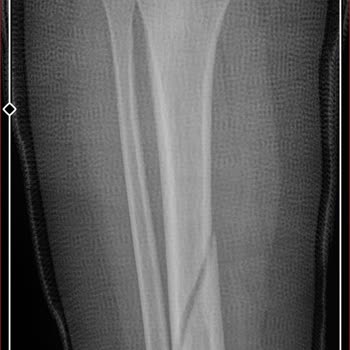

17 Aralık 2025 tarihinde Marmaris’te Vega Ice tarafından işletilen, Marmaris Belediyesi’nden kiralanan buz pistinde oğlumla birlikte çok ciddi bir güvenlik zafiyeti yaşadık. Pistte herhangi bir yaş sınırlaması olmadan ve etkili bir kontrol yapılmadan insanlar kalabalık şekilde içeri alınıyordu. Bu k...